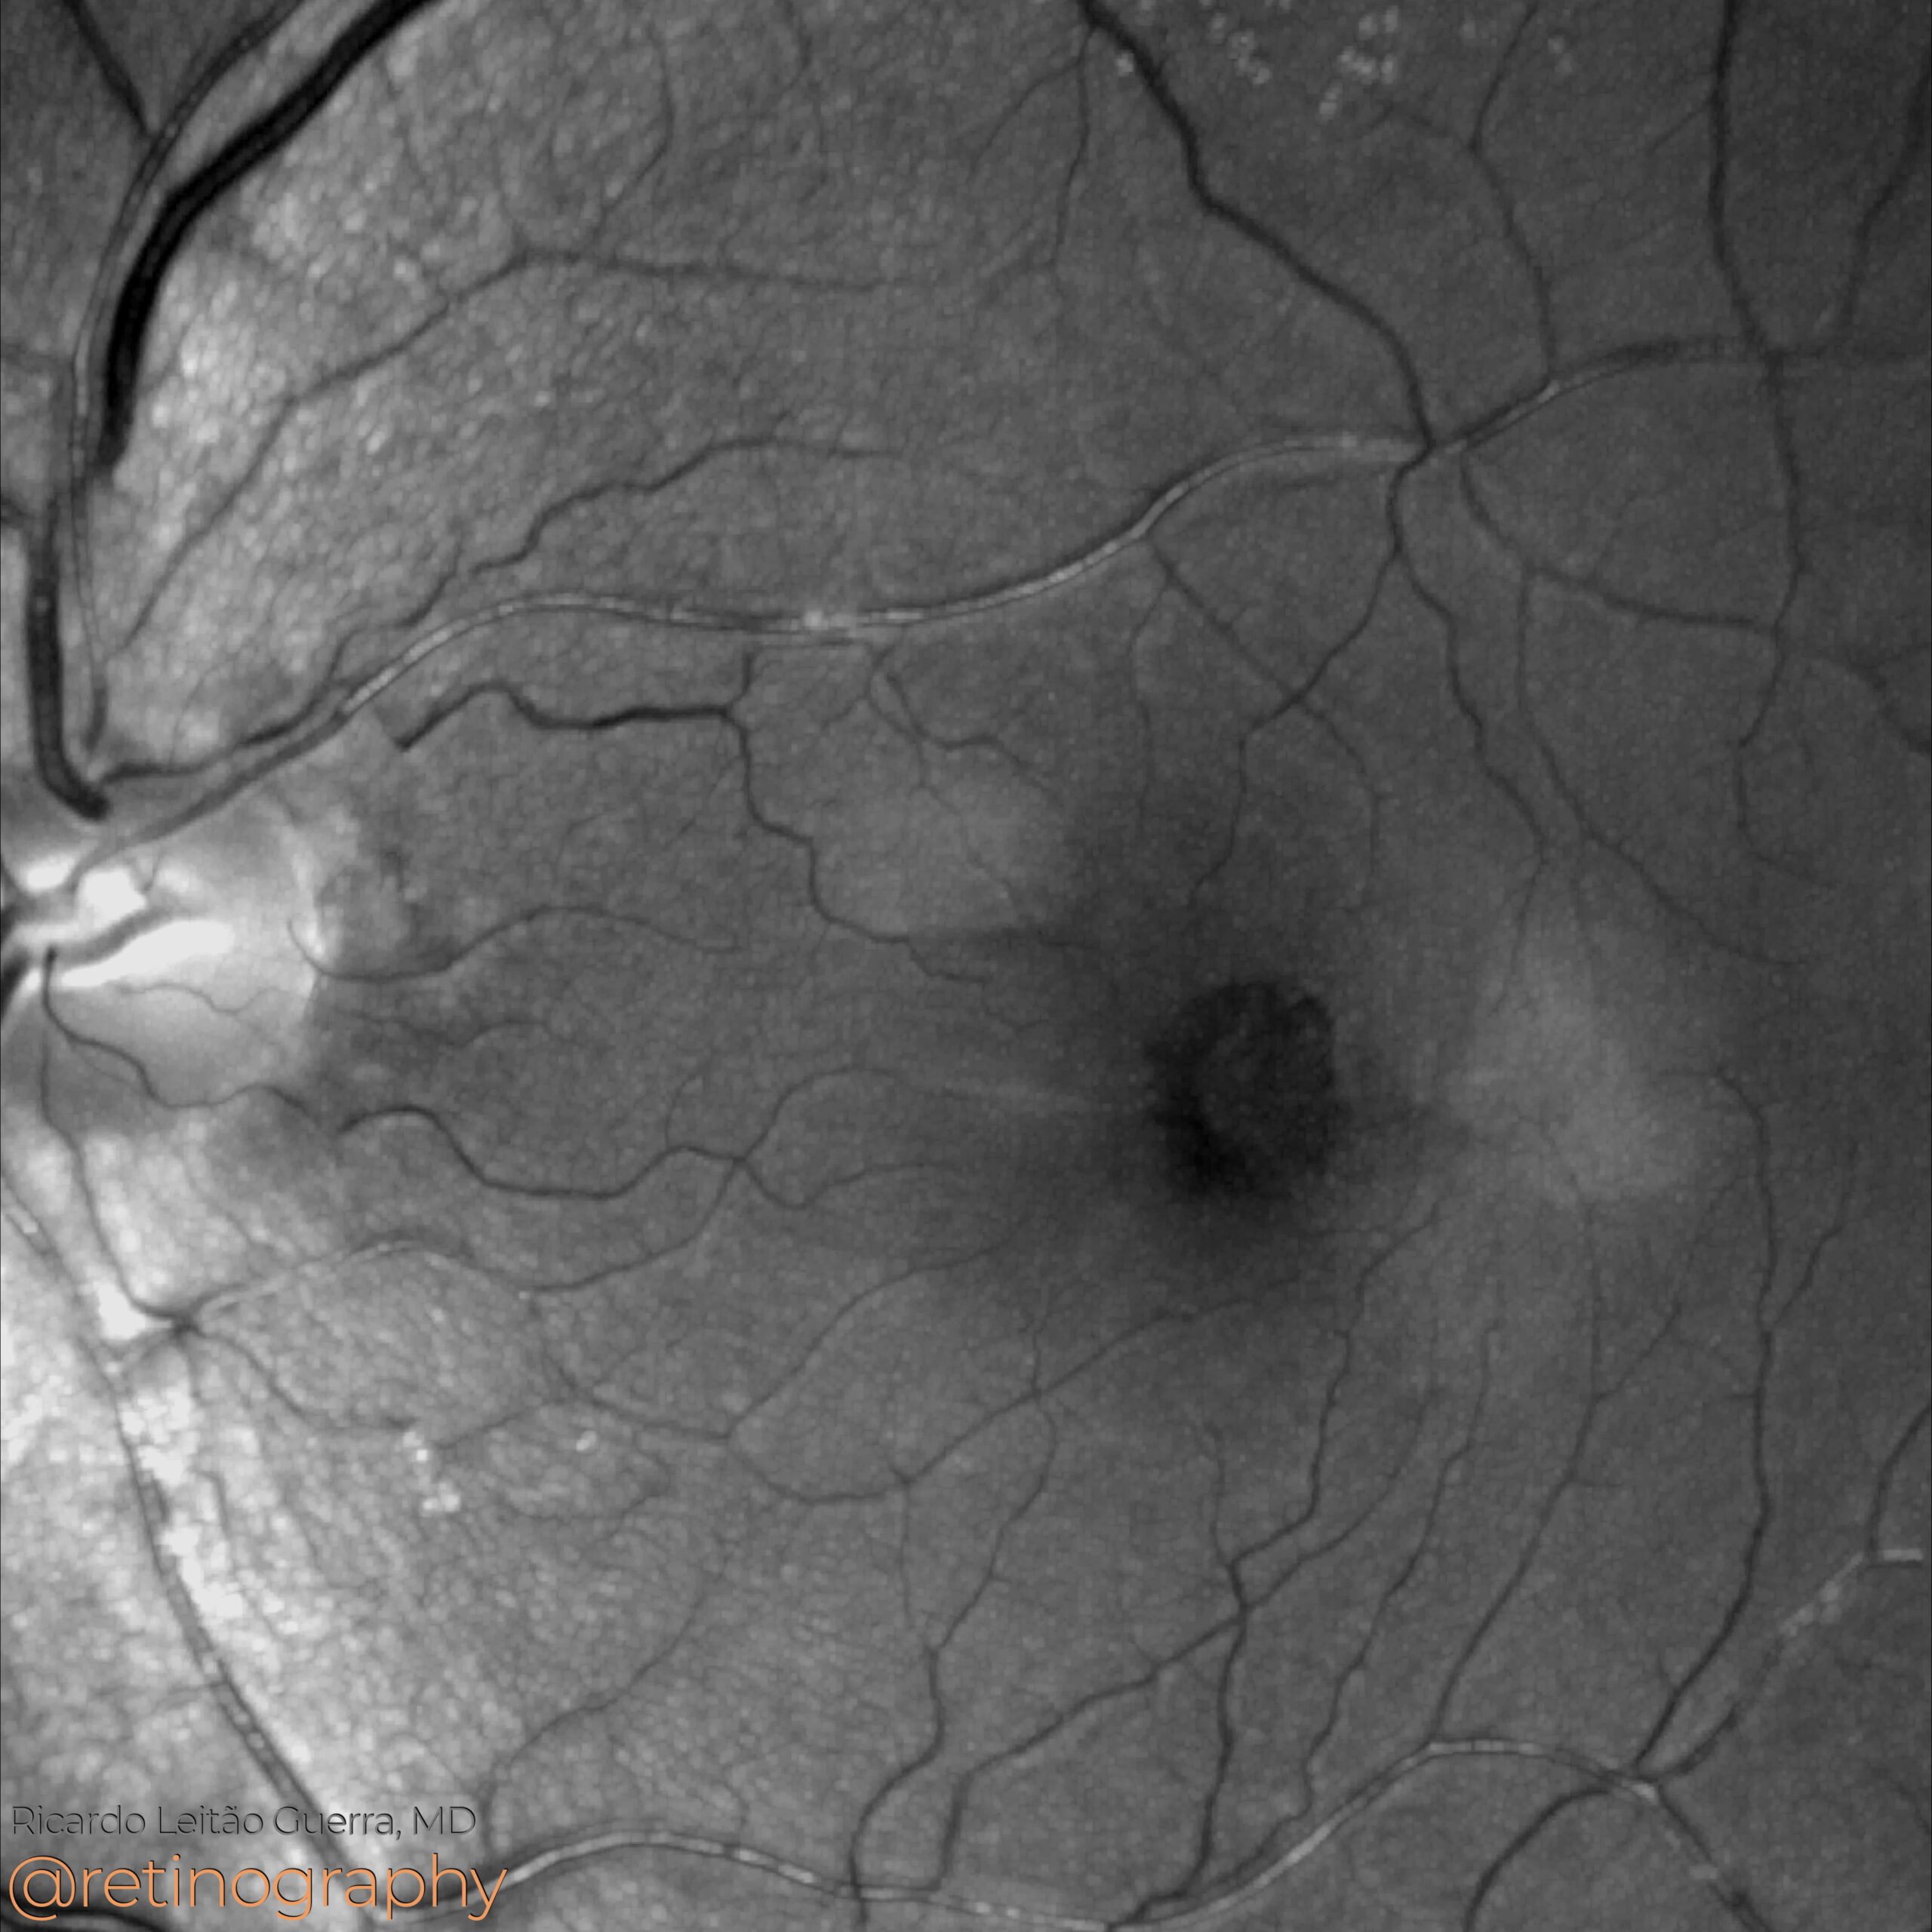

Macular telangiectasia type 2

82yo Macular Telangiectasia Type 2 (MacTel 2) can be monitored with blue light reflectance imaging, which highlights areas of retinal degeneration and structural changes. Over a 1-year follow-up, an increase in the hyperreflectant area indicates disease progression, reflecting the expansion of retinal abnormalities. This imaging modality is crucial for tracking disease evolution.